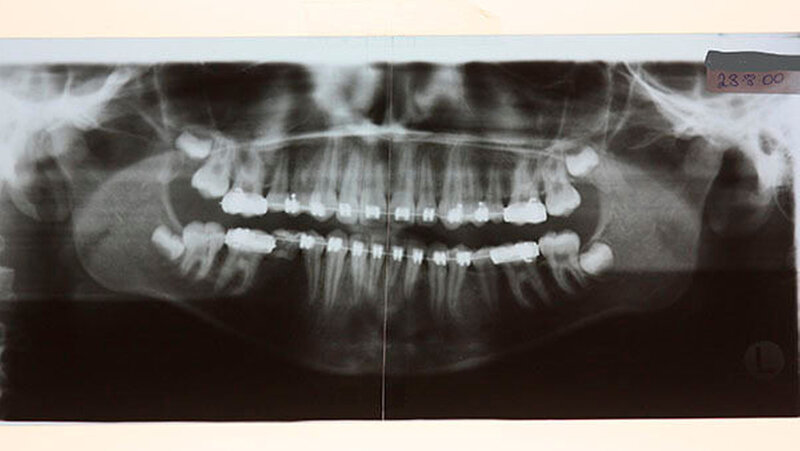

Das Bonner MKG-Chirurgenteam um Prof. Dr. Dr. Rudolf Reich diagnostizierte eine zunehmende Einschmelzung (Resorption) der Kiefergelenkfortsätze, wodurch die gesamte Abstützung des Unterkiefers am Schädel verloren gegangen war.

Die Ursache dieser fortschreitenden Erkrankung kann eine chronische Entzündung wie Rheuma sein, andere Gründe gerade bei jungen Frauen werden zurzeit erforscht. Der Kiefergelenkschwund führt neben den genannten Veränderungen durch Überlastung auch zum vorzeitigen Verlust der hinteren Zähne und in manchen Fällen zur Schlafapnoe.

Mit der virtuellen Planung, individuellen Kiefergelenkprothesen und einer zusätzlichen Rückpositionierung des Oberkiefers in die ursprüngliche Lage erfolgte dann die Operation. Alles erfolgte in einem Operationsgang. Die Bonner MKG-Chirurgen fertigten die Endoprothesen für die Frau individuell im CAD-/CAM-Verfahren an. Dafür wurden die Daten der Computertomografie des Schädels zugrunde gelegt.

Durch diese hoch anspruchsvollen Verfahren ließ sich annähernd die ursprüngliche Position des Unterkiefers vor der Einschmelzung wiederherstellen; in der gleichen Operation wurde die Position des Oberkiefers der jetzt idealen Stellung des Unterkiefers angepasst.

Die Patientin erreicht dauerhaft eine Mundöffnung von 35 mm ohne Schmerzen, kann jede Nahrung zu sich nehmen und hat einen stabilen Zusammenbiss der Zähne - auch die erhebliche Rücklage des Unterkiefers ist dauerhaft beseitigt.